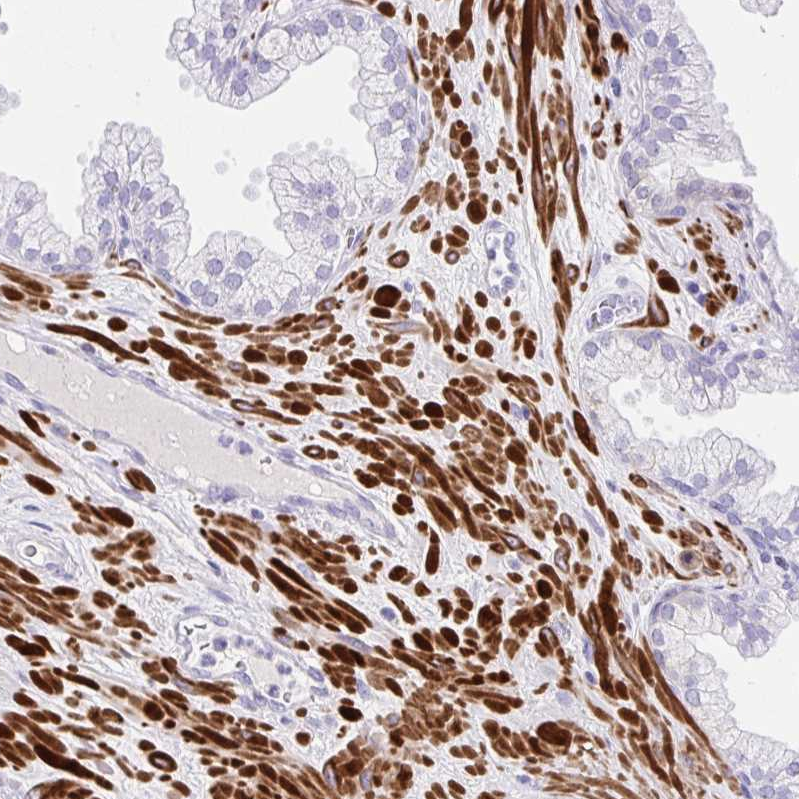

Immunohistochemical staining of human prostate shows strong cytoplasmic positivity in smooth muscle cells.